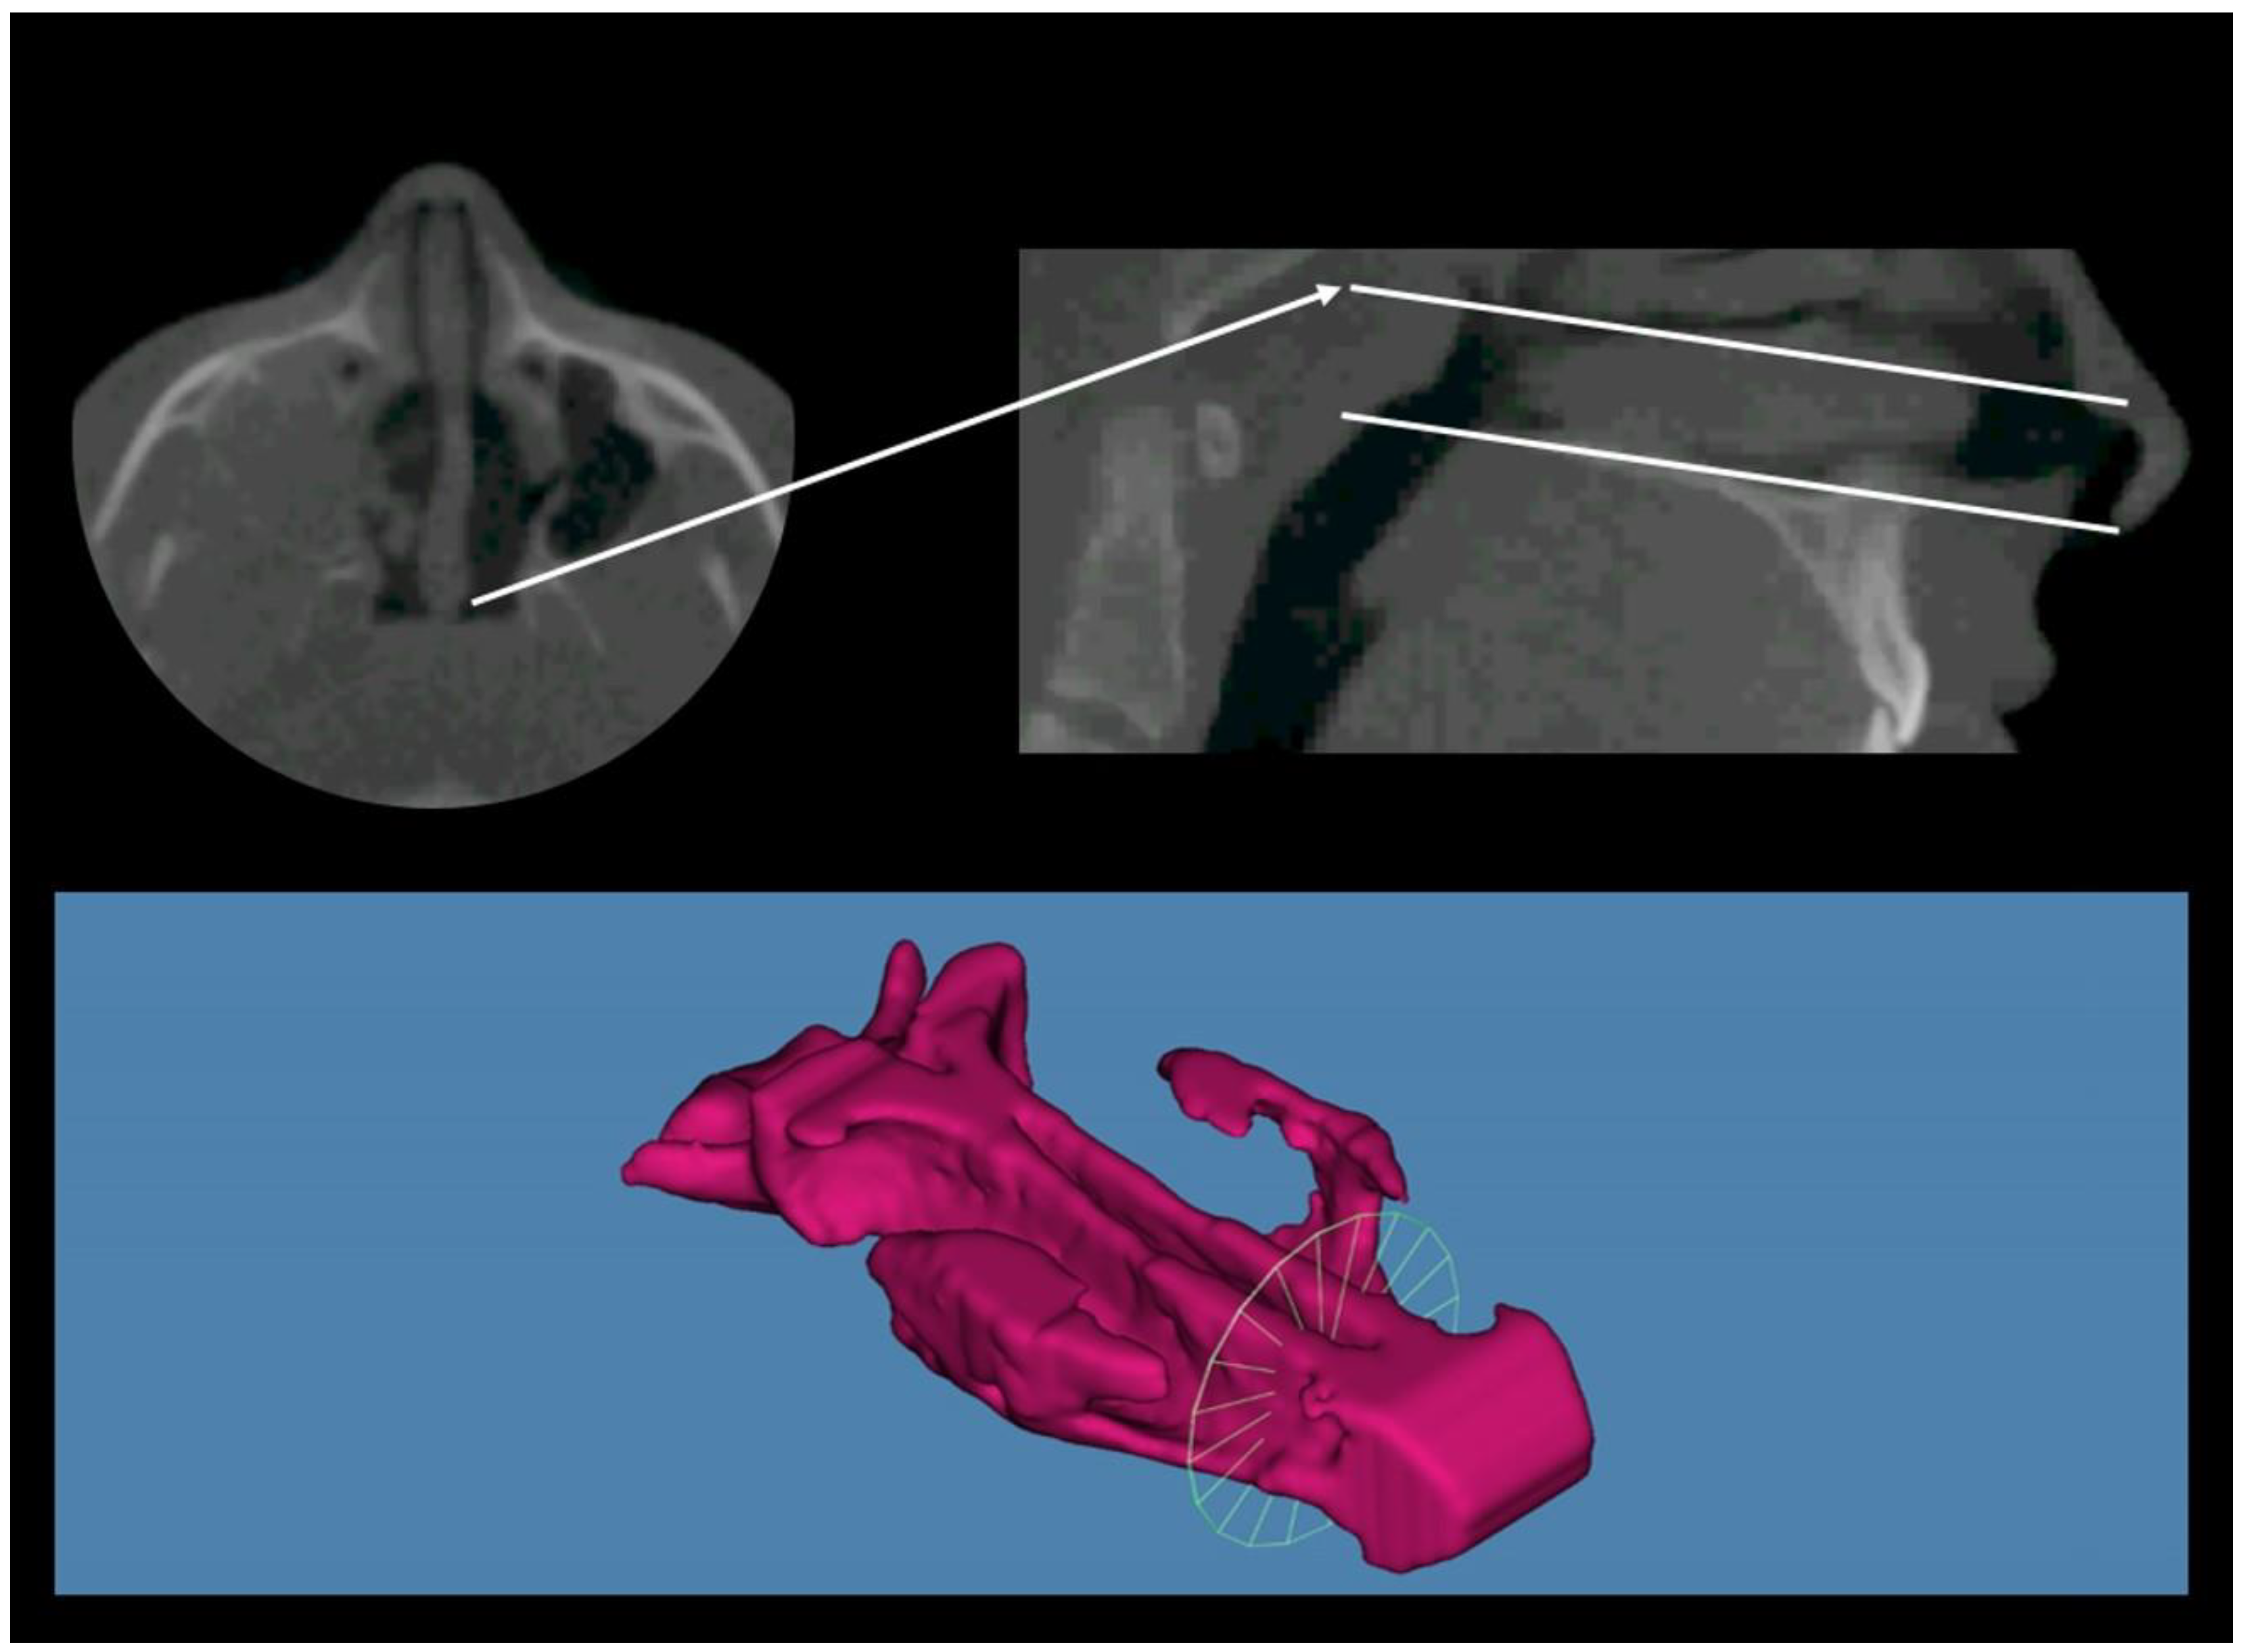

2. Materials and Methods